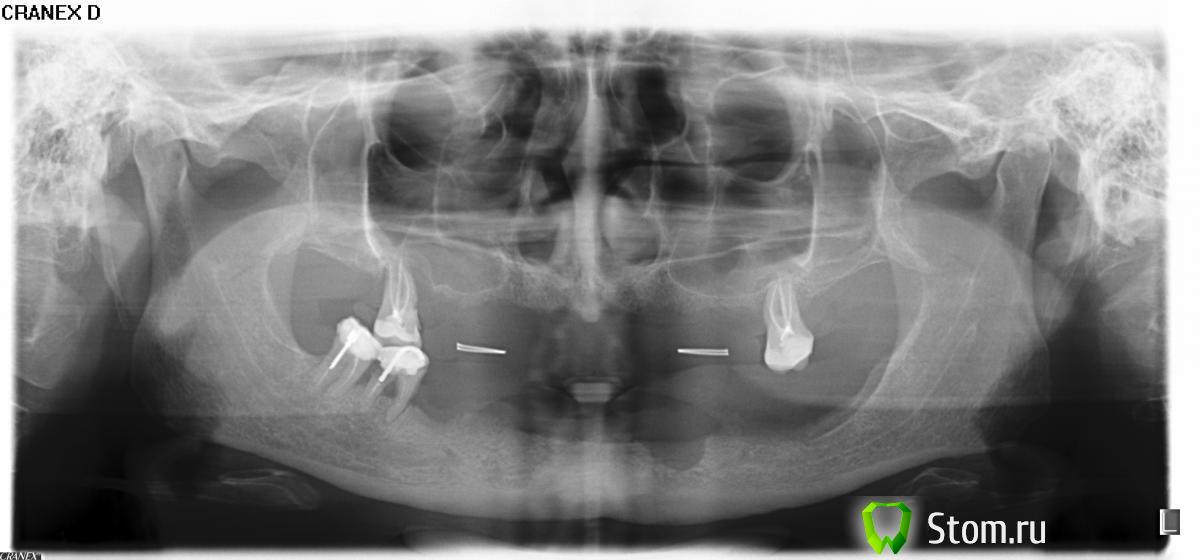

tann13 Опубликовано 13 марта, 2012 Автор Поделиться Опубликовано 13 марта, 2012 Видимо, я плохо объяснила ситуацию, или что-то не так со снимком. Недавно вышел (или выпал?) передний зуб (у меня периодонтит) и протез практически не держится. Нужно что-то решать, склоняюсь к имплантации, но не уверена, что хватает кости- у врачей провоположные мнения. Нужно ли наращивание, или другие дополнительные операции? Ссылка на комментарий

Doc Опубликовано 13 марта, 2012 Поделиться Опубликовано 13 марта, 2012 Я так понял, что речь о нижней челюсти? В таком случае у Вас оптимальный вариант - полный съемный на балке (или замках) на четырех имплантатах. Ничего пересаживать не придется, фиксация насмерть, эстетика идеальная, цена средняя. Ссылка на комментарий

Doc Опубликовано 13 марта, 2012 Поделиться Опубликовано 13 марта, 2012 Без осмотра и КТ сложно говорить, но обычно наверху полный съемный протез тоже держится неплохо, а выглядит хорошо. Так что если с деньгами сложно и не хочется влезать в дорогостоящие и сложные операции, то можно ограничиться полным съемным сверху, четырьмя имплантатами снизу и протезом на них. Если с финансами не проблема, хочется идеала и забыть о протезах на всю оставшуюся жизнь, то скорее всего придется пересаживать кость, ставить минимум 14 имплантатов и делать мосты и сверху и снизу. Ссылка на комментарий